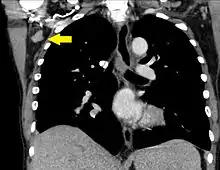

| A CT scan of axillary lymphadenopathy in a 57-year-old man with multiple myeloma. | |

Lymphadenopathy of the axillary lymph nodes can be defined as solid nodes measuring more than 15 mm without fatty hilum.[36] Axillary lymph nodes may be normal up to 30 mm if consisting largely of fat.[36]